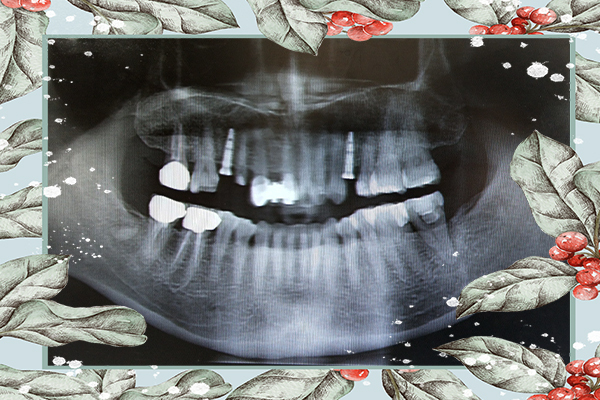

新華牙醫資深院長林義城醫師親自操刀速度又快又準

大約才半小時而已就聽到手術室開門聲

林義城醫師有特別花時間跟我們介紹植體上的螺帽

是為了保護人工牙根不要被異物塞住用(超神奇

約等三到六個月骨頭整合後就可以來診所做牙冠